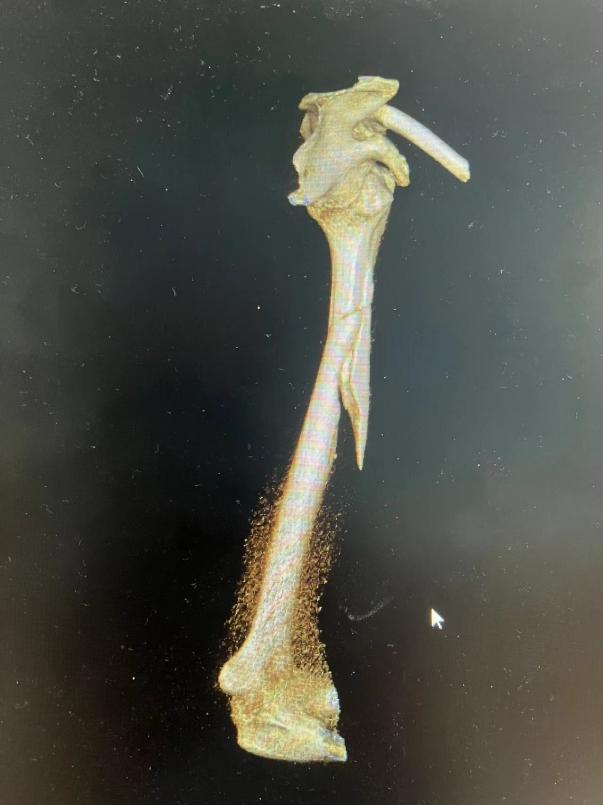

患者受伤时三维CT,可见骨折端粉碎,移位,成角畸形